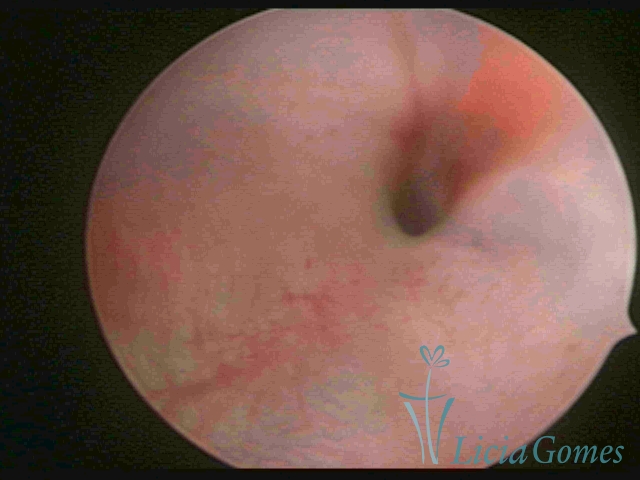

Segunda porção ou setor médio

No terço ou setor médio do canal cervical perdemos o detalhe das papilas, sendo possível a visualização de pregas e criptas. Normalmente observamos os sulcos longitudinais, que são os tecidos mais compactos, com a superfície mais vascularizada, cujos vasos seguem o seu trajeto.